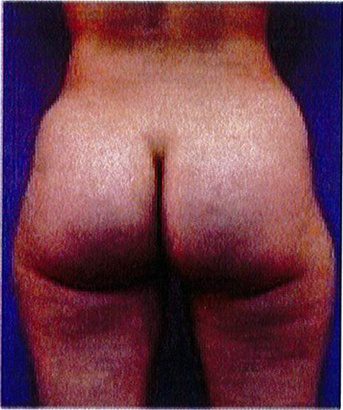

Hình. 18.. (A) Hình anh trước và (B) và sau phẫu thuật làm đầy mông của bệnh nhân được đặt khối implant dưới cân thể tích 225 mL, hai bên.

Bệnh nhân 31 tuổi tiền sử khỏe mạnh, có chỉ định nâng mông bằng implant do thiếu hụt thể tích. Hai khối anatomic implant 225 mL polyurethane dạng gel được đặt ở vị trí dưới cân. Sau phẫu thuật không ghi nhận biến chứng trong suốt quá trình hồi phục, vết mổ liền tốt (Hình 18).